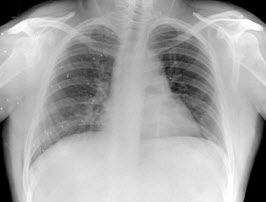

103、单项选择题

早产儿,男,生后6小时,于生后2小时出现呼吸困难,如图,最可能的诊断为()

A.新生儿肺炎

B.新生儿湿肺

C.新生儿肺出血

D.新生儿呼吸窘迫综合症

E.胎粪吸入综合征